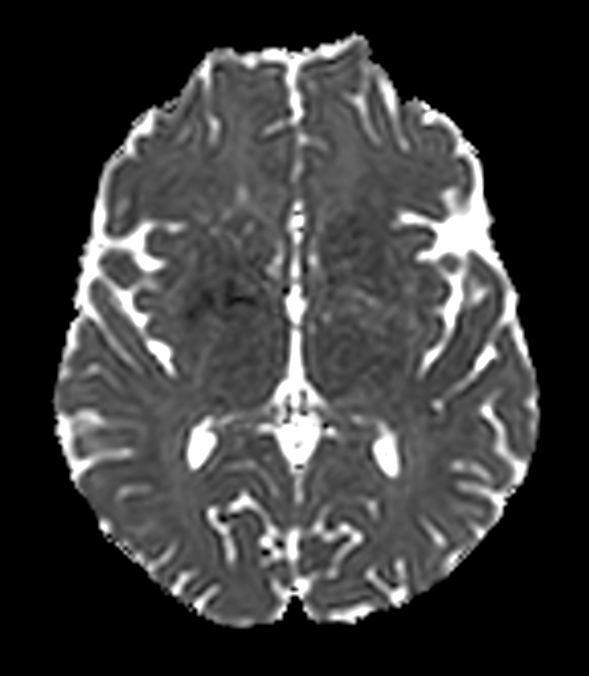

Axial DWI b1000

-